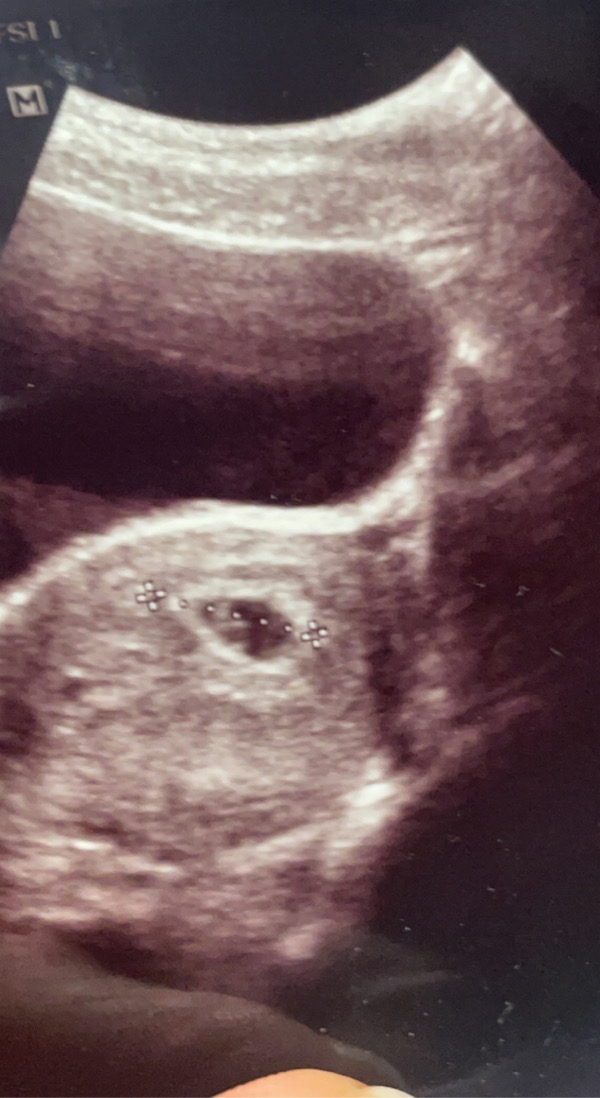

بنات شوفوا السونار سويته بالاسبوع الثامن تقريبا ، بنات تشوفوا جنين ولا بس كيس ؟ وكمان ع حسب النظريه اللي تتكلموا عنها جنيني احتمال يكون بنت ولا ولد ؟